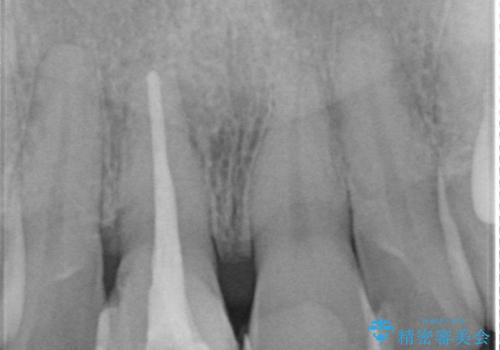

根管治療に伴う歯の色調変化はよく見られる所見です。

セラミッククラウン製作を行い審美性の改善を計画します。

- 15.4万円(仮歯・ファイバーコア・ジルコニアクラウン)費用は治療当時の料金となります